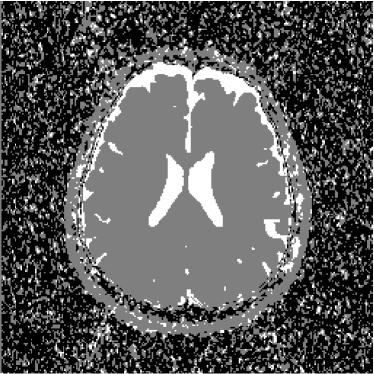

Therefore, the pixels of the ADC map are proportional to the diffusion coefficients in the corresponding voxels. However, as the images are acquired at different moments, there must be considered the occurrence of noise in all the experiments. Furthermore, the presence of noise is amplified by the use of the logarithm. In figures 7 and 8 it is possible to see several artifacts generated by the presence of noise. In regions where signal-to-noise ratio is poor (e.g. s/n1𝑠𝑛1s/n\approx 1), the ADC map produces artifacts as a consequence of the calculation of logarithms (notice equations 4 and 6).

Such factors leave us to the following conclusion: the pixels of the ADC map not necessarily correspond to the diffusion coefficients: several pixels indicate high diffusion rates in voxels where the sample are not present or in very solid areas like bone in the cranial box, as can be seen in figures 7 and 8. This is the reason why such map indicates apparent diffusion coefficients, and not real diffusion coefficients.

Refer to caption

Figure 7: ADC map of 13th slice calculated from the three diffusion images presented in figures 1, 2 and 3